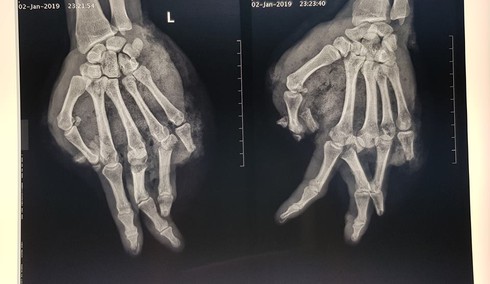

Hình ảnh tay bị tổn thương trên phim chụp |

Qua quá trình thăm khám, bác sĩ Vũ Hữu Trung – Khoa Chấn thương Chi trên và Vi phẫu thuật nhận định bệnh nhân bị tổn thương vết thương phức tạp, dập và lóc da, bầm dập nặng phần mềm bàn tay, dập nát ngón I, V và đốt 2,3 ngón IV; gãy hở nền xương đốt 1 ngón III, IV.

Hiện tại, bệnh nhân đã qua xử trí cắt lọc vết thương, tạo mỏm cụt ngón V; đốt 1 ngón I và ngón IV và khâu da định hướng. Bệnh nhân sẽ tiếp tục được thay băng, chăm sóc vết thương; dự phòng và xử trí hoại tử thứ phát, sau đó từng bước làm liền vết thương.